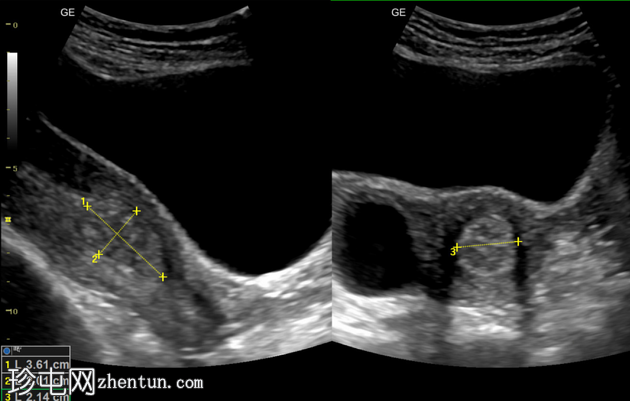

超声

检查

纵切面

横切面

子宫内膜腔内可见边界清晰的高回声病灶,大小为36 x 20 x 21mm,彩色多普勒显示其周围有供血动脉。

子宫内膜腔内可见高回声病灶,并有供血动脉,这是超声检查中子宫内膜息肉的典型特征。患者持续阴道出血一个月。